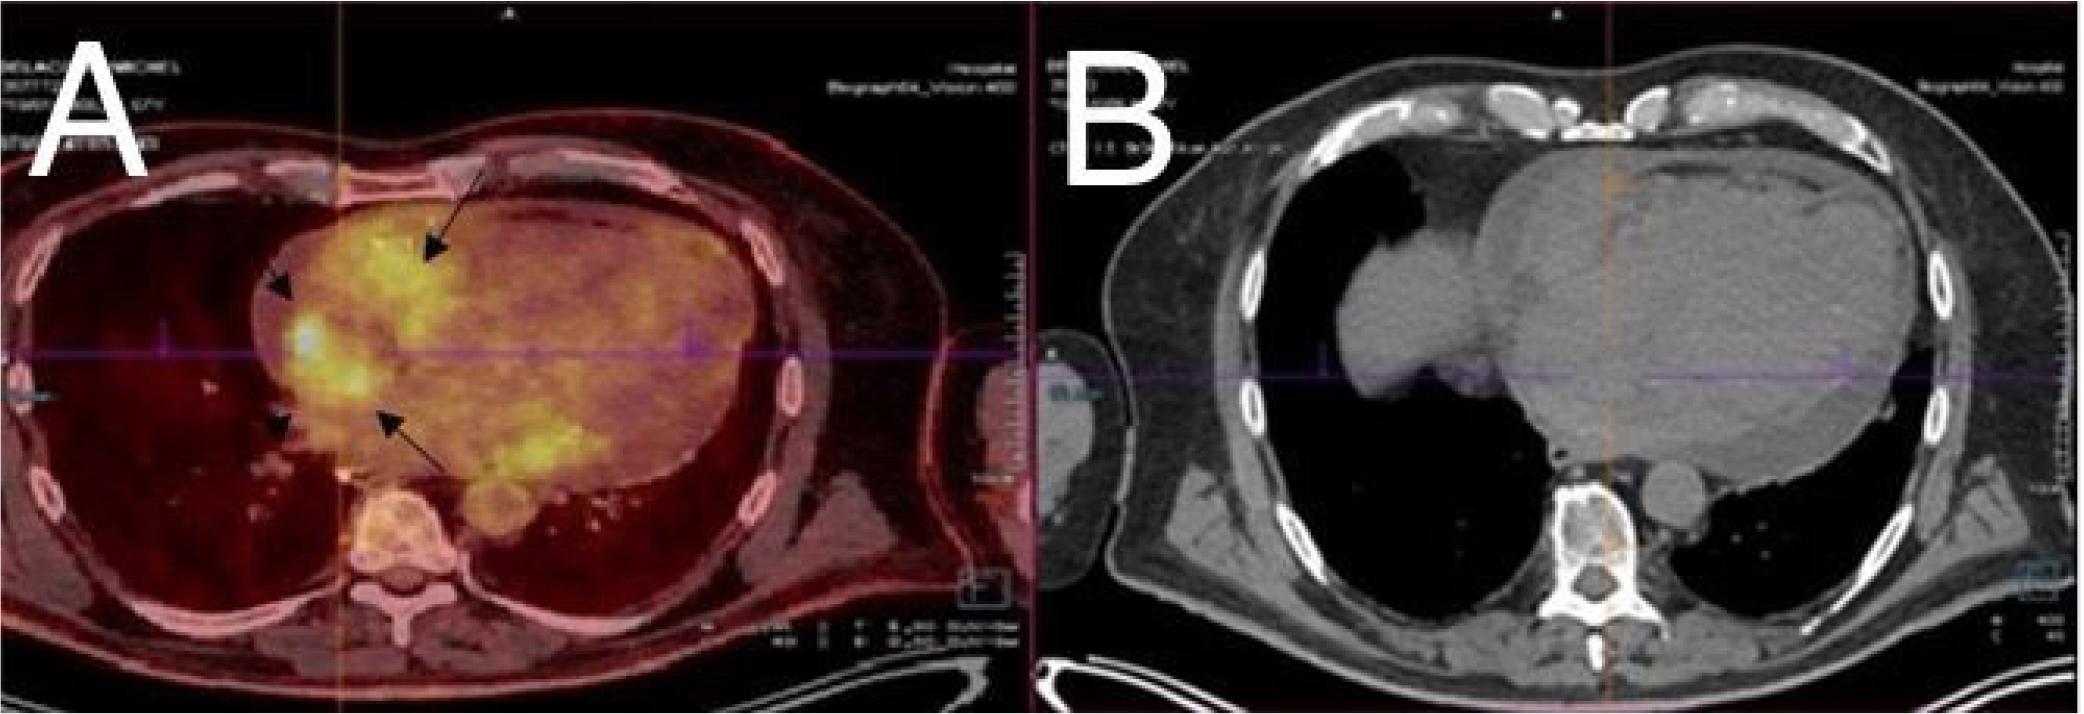

Figure 2